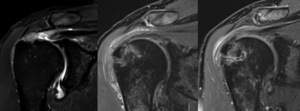

Preoperative RTC tear type and dimensions are listed in Table 2. At both 3 and 6 months postoperatively, each patient underwent MRI evaluation of the affected shoulder. No recurrent rotator cuff tears, failure of the repairs, or effusions were identified (Table 2). The rotator cuff footprint was restored in each case (Table 2). All patients showed early tissue reactions at the 3-month mark in the subacromial space, with thickened tissue corresponding to the area where the HA patch had been placed. By 6 months postoperatively, the amount of reactive bursal tissue and edema had decreased, and the tendon-like tissue continued to organize, maintaining its thickness. All full-thickness RTC tears (n=6) as well as all four “onlay” procedures (n=3 partial thickness, n=1 myotendinous) were healed by 6 months (Table 2). The average tendon thickness at 3 months postoperatively was 7.63 ± 1.30 mm, and by 6 months, it remained stable at 7.61 ± 1.03 mm, both significantly increased from preop thickness of 4.77 ± 0.67 (p<0.001) (Table 3). These findings suggest successful integration of the HA patch and healing of the repaired tendon.

Our study demonstrated early safety and efficacy of the first HA based rotator cuff graft with improvement in all PROMs and no complications. Postoperative MRI showed healed RTC, footprint restoration, and significantly increased tendon thickness similar to a popular Bovine patch (Bokor et al. 2016; 2015). Subacromial reactive changes were seen in all patients at 3 months and resolved with tendinous incorporation and thickening by 6 months (Tables 2 and 3). Although this is very early follow-up, it is important to ensure this new technology is both safe and effective, as there have now been more than 1000 surgical implantations throughout the US (Baker 2025).

Thickening of the rotator cuff tendon either by healing of the tendon itself or by integration of tendon-like tissue is felt to be the main benefit of supplementing RTC repairs with a bursal sided patch (Bokor et al. 2016; 2015). It has been the senior author’s experience that the use of various synthetic and biologic graft augmentations in RTC repair leads to early postoperative reactive “inflammatory like reactions” in the subacromial space. A previous study on the Integrity Implant System in an Ovine model showed progressive implant degradation along with fibroblast neocollagen deposition, and fiber-like organization around the PET component within the RTC throughout the 26 week study (Badylak 2023).

This study revealed similar reactive subacromial changes on postoperative MRI, which likely reflects the graft’s biodegradation and cell mediated immune response corresponding to T2 edema on MRI at 3 months postop (Figures 4 and 5). However, there was ultimate thickening and consolidation of this edematous area into low signal tendon-like tissue in the RTC at 6 months, which may indicate a completed healing response, and partial degradation and structural incorporation of the graft. This study also shows similar thickening and healing of both partial thickness and full thickness RTC tear patients, with ultimate consolidation into a single continuous tendon complex. Previous studies measuring RTC tendon thickness after repair in the absence of patch augmentation most commonly show reduced tendon thickness compared to preoperative ipsilateral as well as contralateral measurements (Kjaer et al. 2024; Crim et al. 2010; Tham et al. 2013). However, one study reported a small proportion of patients did undergo tendon thickening compared to preoperatively (Crim et al. 2010). It was felt important to characterize the expected imaging characteristics of the HA patch in short intervals of 3 and 6 months postop to inform physicians of the thickened subacromial appearance and investigate tendinous healing and graft incorporation radiologically. We reported significant increase in average tendon thickness from 4.77 ± 0.67 mm to 7.63 ± 1.30 mm at 3 months (p<0.001), and 7.61 ± 1.03 mm at 6 months (p<0.001), which is similar to published data for a commonly used bovine collagen patch that reported mean tendon thickness at 6 months postop as 7.6 mm for men and 7.0 mm for women (Bokor et al. 2015). This is noticeably thicker than ultrasound measured supraspinatus thickness at the same timepoint, being 5.6 mm for men and 4.9 mm for women on average (Karthikeyan et al. 2014).